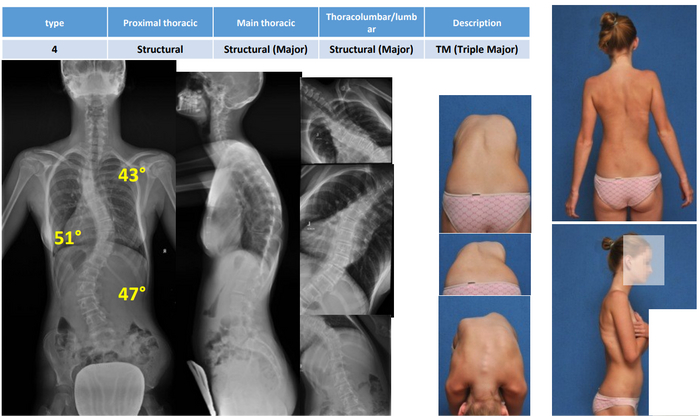

Сколиоз развился около десяти лет, диагноз идиопатический сколиоз. 4 степени.

На момент обследования и фото мне было 13 лет, операцию делали через пол года. и через год после этого "пришла слава" в виде публикации статьи с моим случаем.

Моя спина попала в учебное пособие по коррекции сколиоза, когда я ездила в Европу на операцию )) Операция прошла успешно )

Когда трава была зеленее, деревья высокие, а мне стукнуло 12, обнаружился у меня сколиоз. Это искривление позвоночника, да не простое, не золотое (хотя, судя по тому, сколько было влуплено в мою спину, платиновое). Короче, S-образное. И понесли ботинки Лилю по всевозможным спорткружкам, массажам, лфк, методикам Бубновского, Дикуля, Хуикуля, потому что врачи уверяли, что спорт укрепляет мышечный каркас, и спину косоёбить не будет. Спойлер: будет. И ещё как. В МОЕМ СЛУЧАЕ!

Причины сколиоза не выявлены до сих пор. Травм у меня не было, все родственники до 7 колена ровные как струнки, одна я кривая, что турецкая сабля. Итого. В 15 лет меня скосило до 76°, в подарок – два горба😁 3 года упорных тренировок ушло в жопу. И в горбы.